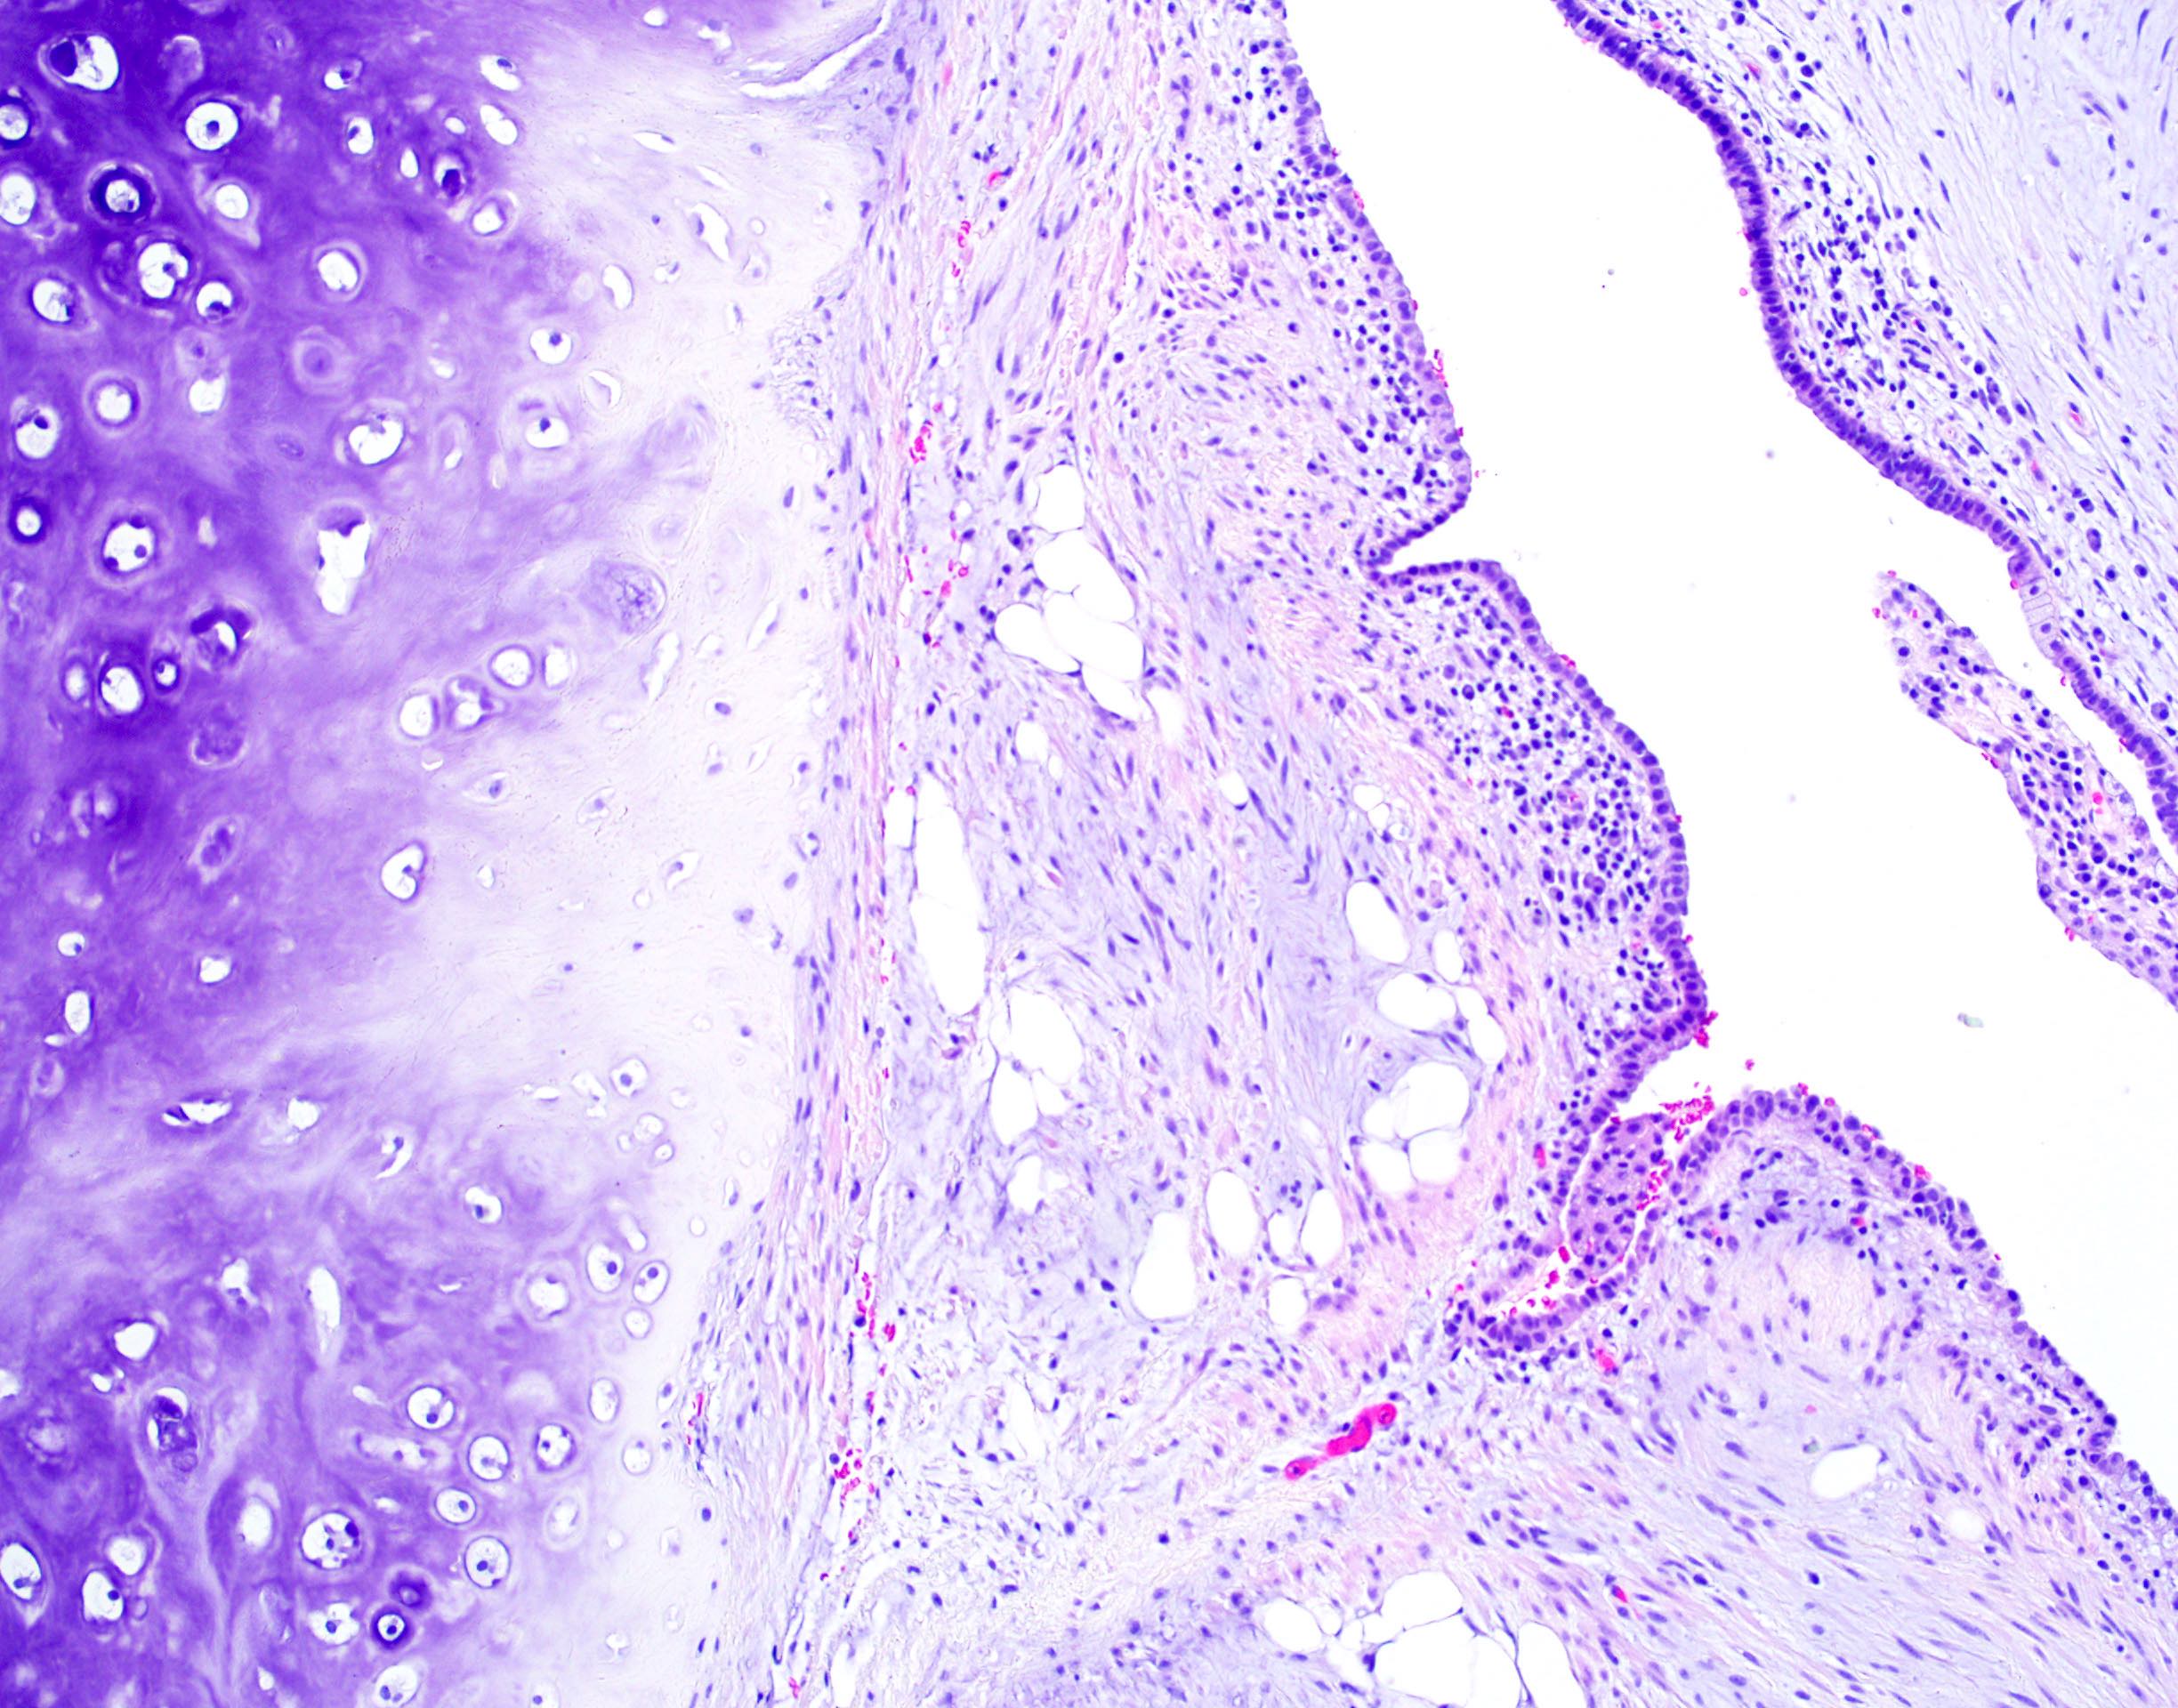

Microscopic (histologic) description

- Composed predominantly of varying degrees of mesenchymal tissue: hyaline cartilage, fat, smooth muscle and bone

- Other connective tissue elements may be present, represented by bland spindle cells, fibrous tissue or myxoid change

- Variably conspicuous, entrapped benign epithelial cells

- Reference: Thorax 1987;42:790

Microscopic (histologic) images

Contributed by Hui-Hua Li, M.D., Ph.D. and Jefree J. Schulte, M.D.

Contributed by @Andrew_Fltv on Twitter